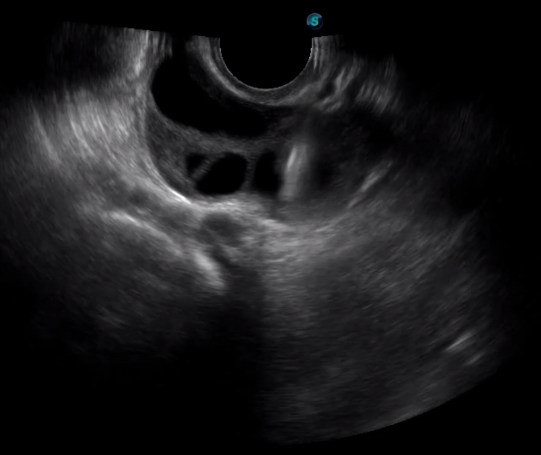

多數(shù)的生殖科醫(yī)生對于受精卵的植入采用憑經(jīng)驗操作或是使用傳統(tǒng)腔內(nèi)探頭引導(dǎo),同樣存在手術(shù)空間小、受精卵放置位置不確定等風(fēng)險。專業(yè)的宮腔專用探頭,配合專用的窺器使用,為醫(yī)生提供最大的手術(shù)視野。

胎移植臨床圖